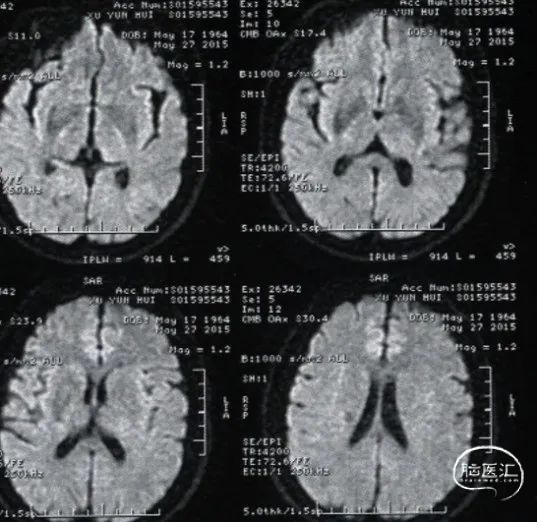

复查头颅MRI:无新发脑梗。